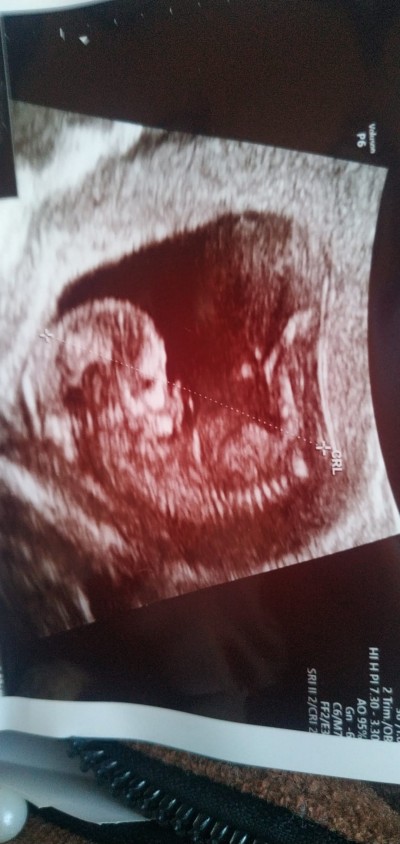

Cinsiyet tahmini yapabilen var mi hanimlar durusundan falan anlasilir diyorladi sormak istedim

Gebelik haftası 13

Erkek gibi geldi ama